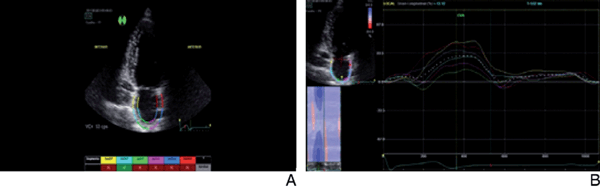

A continuación, se realizó el seguimiento automático del área de interés y se calificó automáticamente en aprobado o no aprobado. Para la realización de nuestro protocolo se desestimó la aprobación automática del seguimiento y se priorizó el juicio del observador (Figura 4 A y B).

Figura 4: A) Ilustración del seguimiento de strain donde se define la región de interés desde el borde endocárdico, adecuando el ancho de la región de interés al mínimo disponible del software. Nótese la no inclusión del anillo mitral dentro de la región de interés. Un aspecto importante es que el software aprueba solamente un segmento de los seis evaluados, pero se observa un seguimiento armónico y continuo por parte del trazado (figura 4B) de todas las fases de la función auricular. B) Ilustración del registro de strain auricular luego de proceder a pesar de que el software no aprobó la mayoría de los segmentos. Obsérvese el correcto registro y la sincronía del movimiento de todos los segmentos auriculares acorde a cada fase auricular.